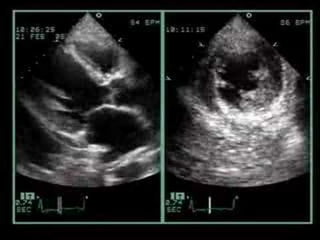

APICAL